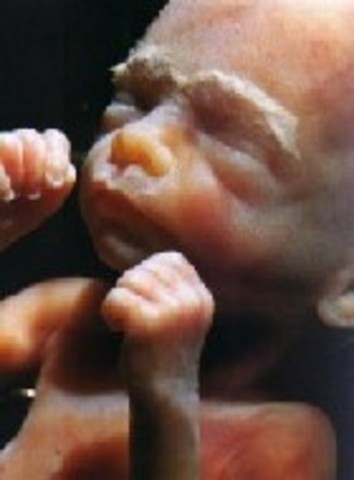

week 15

Baby can now make a fist. Fingernails and toenails are now present.

• week 16

week 16

Fat begins to form underneath skin.Baby hears external voices